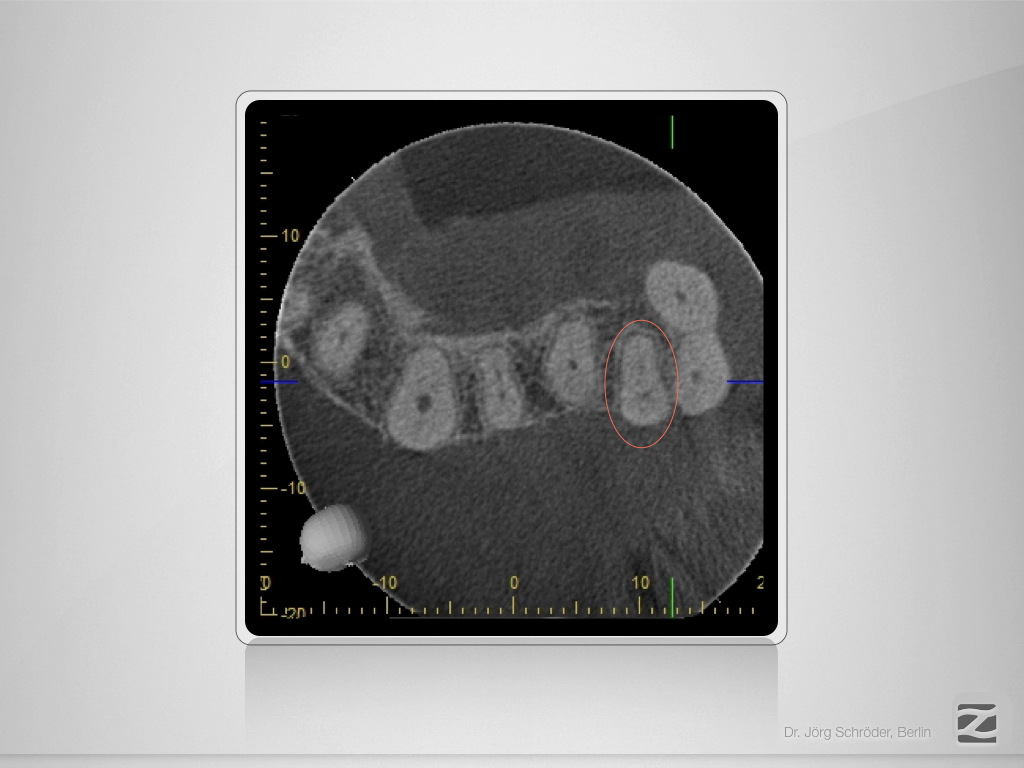

26D.002

Kurventechnik